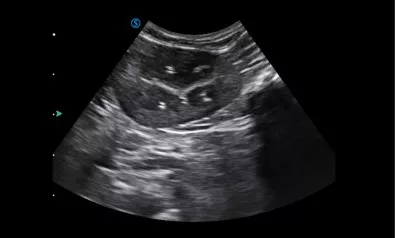

VP2 provides various applications for veterinary diagnosis with micro convex probe and linear probe.

Kidney